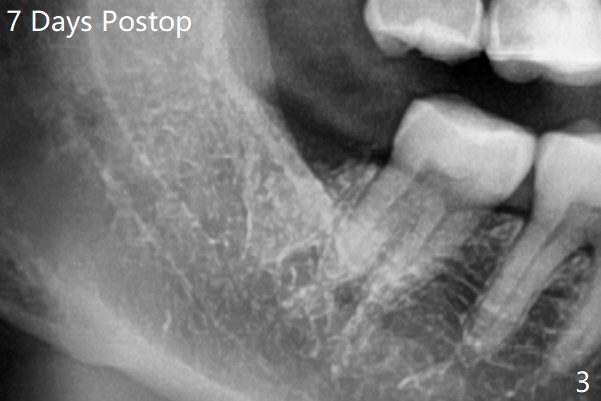

术前外斜脊(图一:*)存在,术后即刻没有消失,放置0.5毫升骨水泥(图二)。术后七天左下牙槽窝上部或者全部骨水泥丢失(图三)。